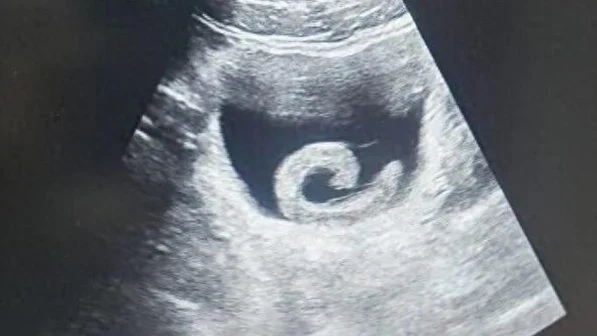

为了生存,它不停往更深处前进,最终爬到了膀胱,牢牢吸附在膀胱壁上,释放抗凝血物质,以血为食。

实在难以忍受,男子随后向医院求助,最终是通过手术将异物取出来了。